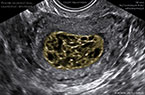

Grossesse môlaire (môle complète) - Aspect échographique - الحمل العدارية أو الرحى العدارية Grossesse môlaire (môle complète) - Aspect échographique - الحمل العدارية أو الرحى العدارية Grossesse môlaire (môle complète) - Aspect échographique - الحمل العدارية أو الرحى العدارية

Grossesse môlaire volumineuse de 739 ml de volume Grossesse môlaire volumineuse de 739 ml de volume Grossesse môlaire volumineuse de 739 ml de volume